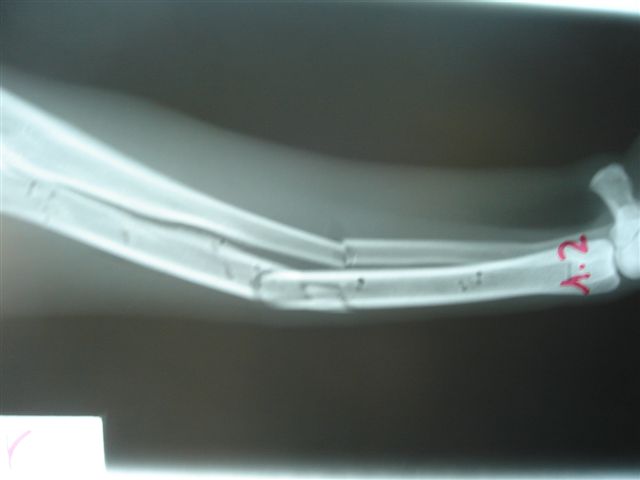

Fijación Externa en IVOT

Fijación Externa

IX CURSO BASICO DE FIJACION EXTERNA.

Casos prácticos alumnos.